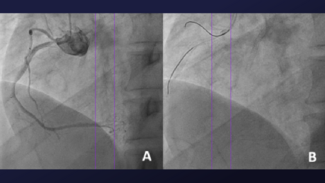

The authors describe an aorto-ostial stenting technique that uses a dual-lumen catheter and floating wire to back a JR4 guide away from a protruding stent while maintaining stability for another guidewire to enter.